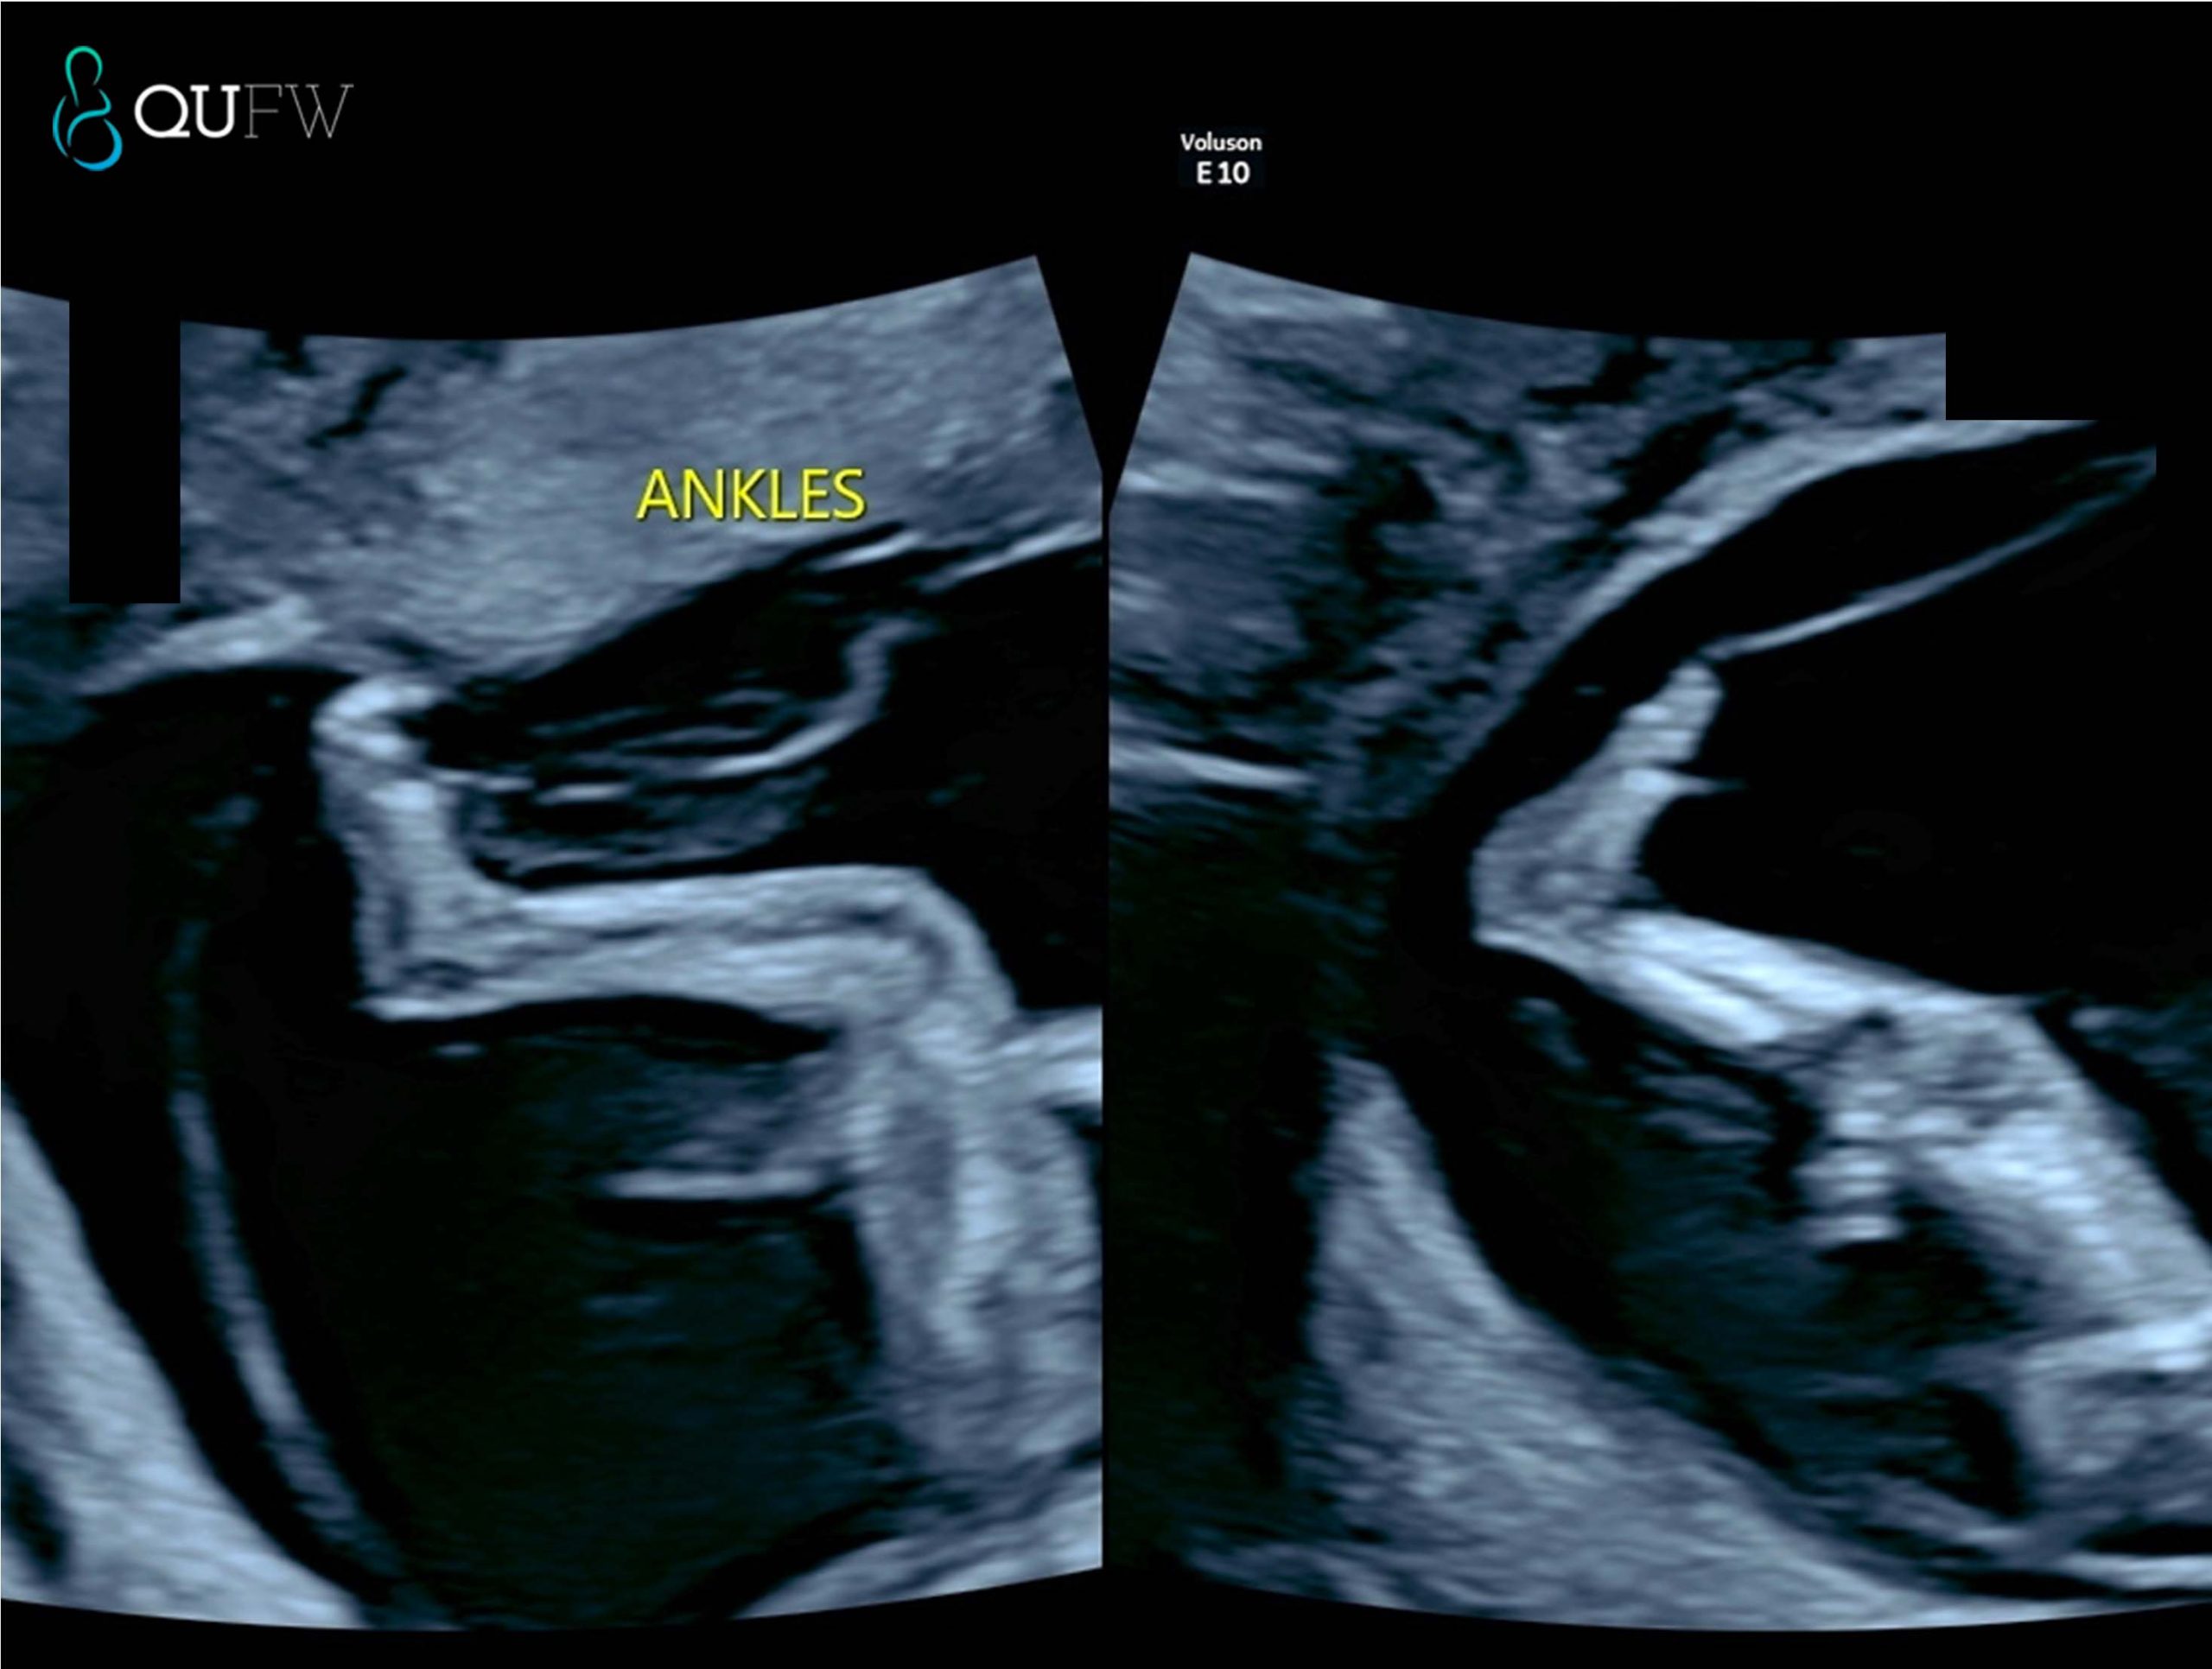

- Extremities – upper limbs/lower limbs including hands and feet

Early structural assessment of the lower limbs